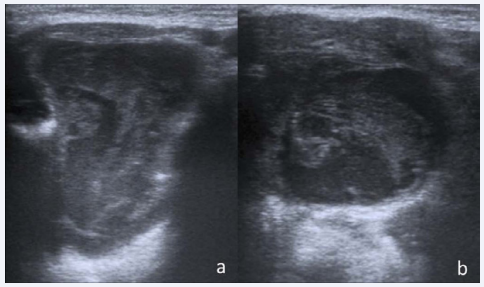

An 8-year-old male patient presented with a painless submandibular swelling, without fever or history of trauma. He came to our emergency departmentwithaweek-long history of a slowly enlargingleft neck mass. Physical examination revealed a soft submental mass extending into submandibularregion. There were noabnormalities of submandibular skin. The patient complained difficulties with speech, mastication and swallowing. An ultrasound scan (US) showed, in the floor of the mouth, a large complex mass measuring 5x4 cm, well-circumscribed, with heterogeneous echogenicity and unilocular morphology (Figure 1).

Figure 1 US images of large complex mass

(a,b) Trasversal (a) and oblique (b) ultrasound (US) images US images show a huge mass of 5x4 cm, with heterogeneous echogenicity, and convoluted morphology

There was no relationship with hyoid bone and no vascular signals were recognized at color Doppler US; there was noevidence of pathologicallyenlarged lymph nodes.